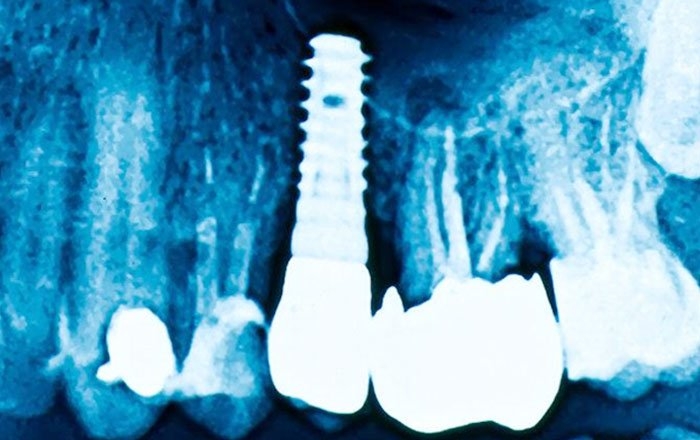

インプラント治療を成功させるためには、コラムでも解説した、インプラント体と顎の骨がしっかりと結合するオッセオインテグレーションが必須です。

骨強度は、骨の量を示す骨密度と、骨の構造や質といった骨質の2つの要素で決まります。一般的に、骨強度への寄与率は骨密度が約7割、骨質が約3割と言われますが、この骨強度が低いと、インプラント体と骨が十分に結合しにくい傾向があるのです。

インプラント治療を行う前には、インプラント治療を受ける前に必要な検査とは?のコラムでお伝えしたように、通常、CT撮影によって顎の骨の量や形状を詳細に評価します。

しかし、CT検査で主に評価できるのは骨密度であり、骨の微細な構造や材質といった骨質までを正確に把握することは難しいのが現状です。

そのため、骨粗しょう症の方の場合、実際の骨強度がどの程度なのかを、術前に完全に予測することは容易ではありません。